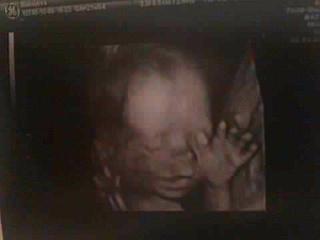

@denne73 jeeejjjj ale je to male krasne 😵 normalne mi nejde do hlavy ze take nieco sa nachadza aj v mojom brusku waw 😕 😕 😵